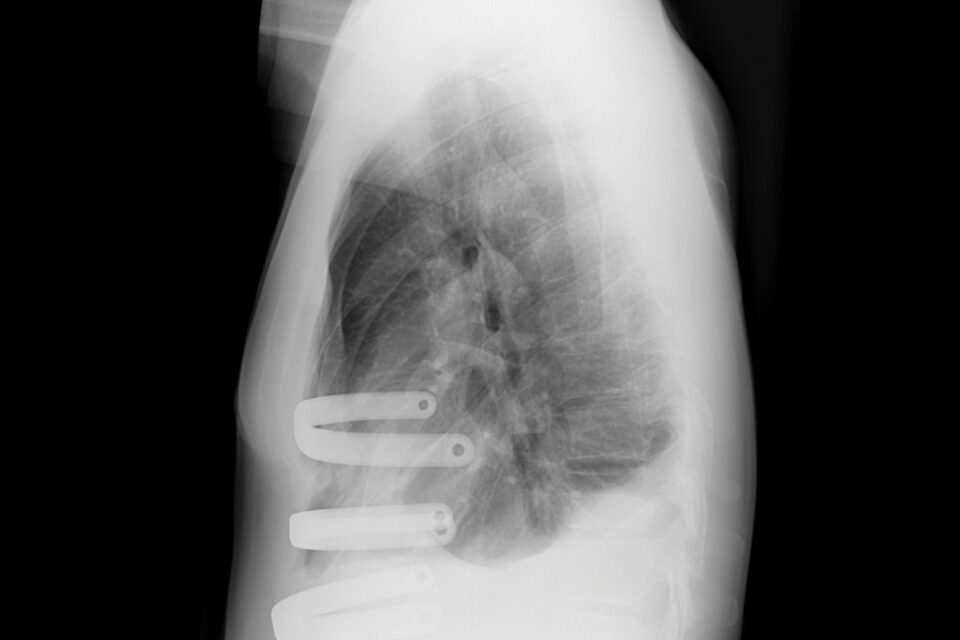

The minimally invasive repair of adult pectus excavatum required cryoablation and three titanium bars, but the patient went home the next day.